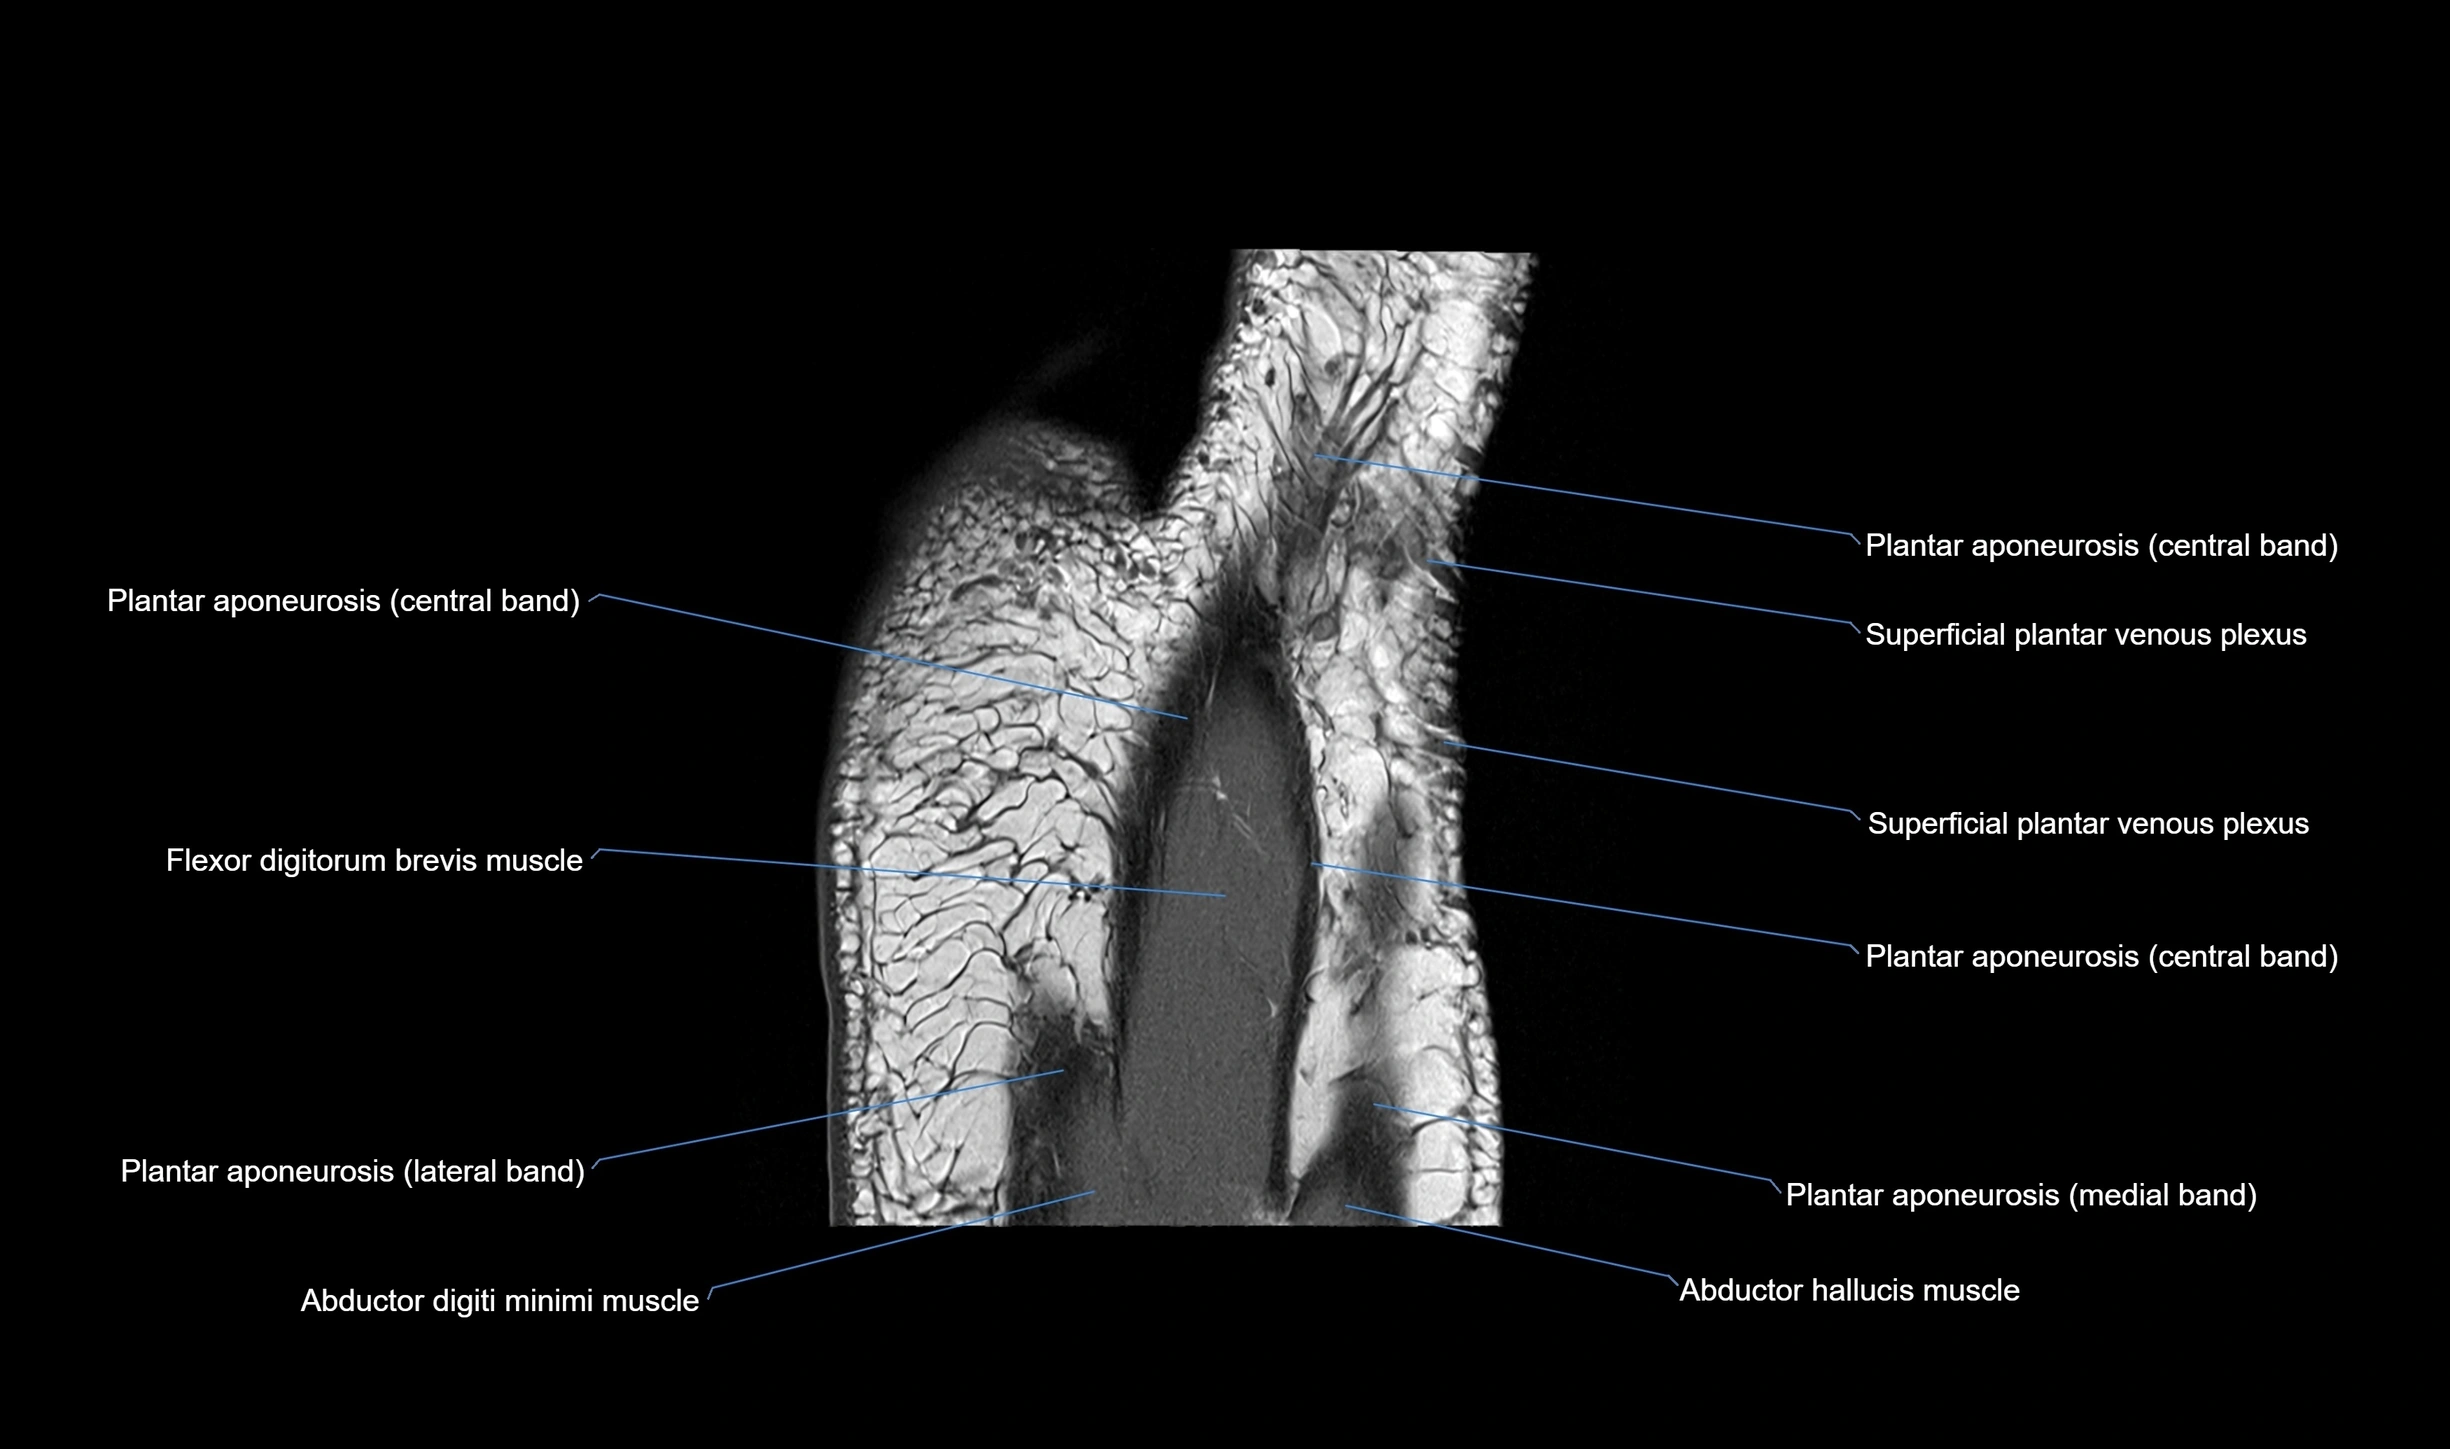

MRI image